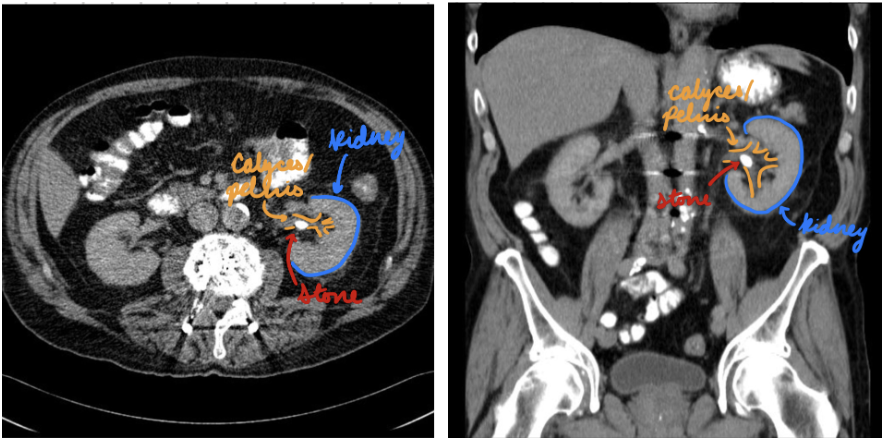

Nephrolithiasis: CT

Gold standard

Stones/calcifications in kidneys and ureters

Determine size, location, density, and degree of obstruction